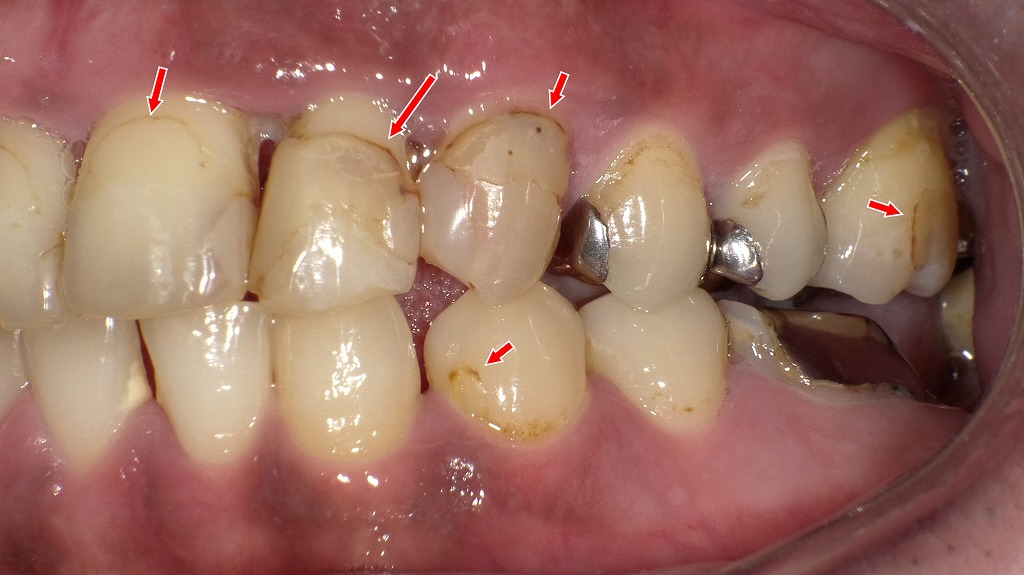

前歯から奥歯まで広がる重度の歯頸部う蝕症例

歯と歯ぐきの境目(歯頚部)に発生した虫歯の症例です。治療前には、歯頚部う蝕や既存のコンポジットレジン充填の変色、二次カリエスが認められました。虫歯を除去した後、コンポジットレジン充填により形態と審美性を回復しています。今回治療した部位以外の虫歯についても、順次コンポジットレジン充填を行い、口腔内全体の健康維持を図っていきます。